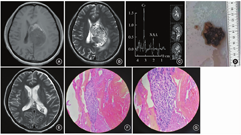

患者 女,45岁,因"右侧肢体麻木、无力半个月余,头晕2 d"入院。入院体格检查:神志清楚,对答切题,遵嘱动作,格拉斯哥昏迷评分(GCS)为15分。双侧瞳孔等圆、等大,直径约为2.5 mm,对光反射灵敏。颈强直(-),四肢肌力、肌张力检查未见明显异常。生理反射存在,病理反射未引出。半个月前于外院门诊行头颅CT检查显示左侧侧脑室内一占位性病变,最大直径约为3.5 cm。入院后第5天,患者的头晕症状明显加重,并出现嗜睡,予20%甘露醇静脉滴注后症状缓解。急诊行头颅MRI、弥散加权成像(DWI)和磁共振波谱(MRS)检查,MRI结果提示:左侧侧脑室体部可见一类圆形异常信号影,边界尚清,大小约为60 mm×43 mm×40 mm,病灶T1加权成像(T1WI)呈稍低信号,前缘可见斑片状高信号灶,T2加权成像(T2WI)呈混杂信号,以稍高信号为主,其内可见多发小囊变区(图1A,B)。DWI可见明显弥散受限,病灶周围可见大片水肿带,中线结向右侧偏移约12 mm。MRS结果显示,病灶区域乙酰天冬氨酸(NAA)峰明显降低,胆碱(Cho)峰明显升高,NAA/(Cho+肌酐)比值倒置(图1C)。考虑到肿瘤生长迅速,于入院后第2天行肿瘤切除术。在气管插管全身麻醉下,取右侧顶部"马蹄"形切口,经顶下小叶皮质造瘘进入4 cm后,可见血运丰富的鱼肉样肿瘤组织,质地不硬,伴有瘤内出血(图1D)。予快速瘤内减压,以吸引器和取瘤镊沿肿瘤边缘探查,发现肿瘤供血血管后予以电凝,打开侧脑室壁,彻底清除脑室内残留的血肿。术后第2天复查MRI显示肿瘤完整切除(图1E)。术后HE染色结果显示,病变由异型细胞构成,可见多核瘤巨细胞和核分裂象,以及大片坏死及横纹肌样细胞,间质可见黏液样变性(图1F,G)。术后免疫组织化学结果提示:INI-1(未缺失)、CD99(-)、Syn(-)、CD34(-)、STAT6(-)、BRAFV6OOE(-)、SSTR2(少灶+)、MyoDl(-)、Myogenin(-),病变符合(颅内)高级别肿瘤。鉴于根据免疫组织化学结果未能明确其病理学分型,行高通量基因检测(NGS二代测序)明确有无特殊的分子遗传学特征,分子检测结果提示:体细胞变异CIC-NUTM1融合(+),病变符合(颅内)CIC重排肉瘤。术后患者未诉特殊不适,无抽搐发作,左侧肢体肌力为Ⅳ+级,余无明显神经系统功能障碍。术后于外院继续行放射治疗。